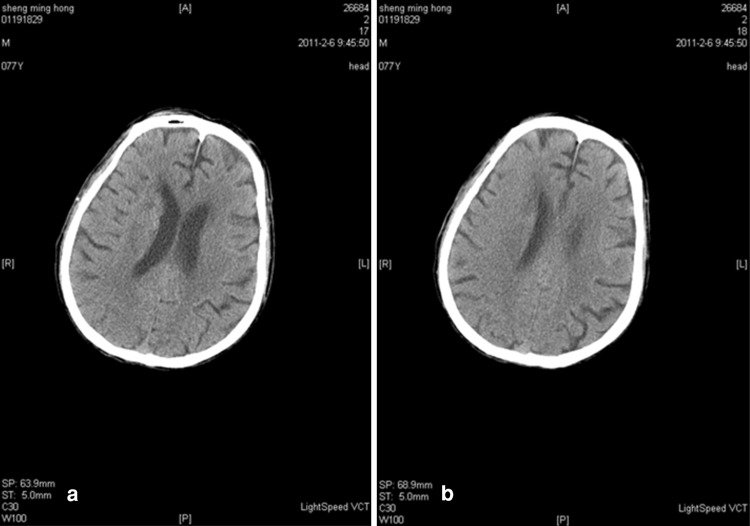

Upon hospital admission, urine flow cytometric analysis was normal, and renal function tests indicated third stage CKD (Table 2). During hospitalization, blood analysis showed that white blood cells were 8.20 g/l (the reference range was 4–10 g/l) and neutrophils were 91.90 % (the reference range was 50–70 %). Chest X-rays indicated infection in the lower sections of both lungs. A color Doppler ultrasound probe of the urinary system showed that the kidneys were normal with smooth encapsulated membranes. The left kidney section was 102 × 51 × 45 mm, and the right kidney was 94 × 49 × 44 mm. In addition, the renal-to-renal sinus proportion was normal; there was no separation between the renal pelvis and calyces, no expansion of the ureter, and no abnormal echo in the bladder area. Blood flow was significantly elevated in the initial renal artery segments, and the resistance index was high, which suggested that the initial renal artery segments were mildly stenotic (Table 3) [4]. Three days after the cerebral infarction, urine flow cytometry was normal. Blood gas analysis showed a pH of 7.531 (the reference range was 7.35–7.45), a carbon dioxide partial pressure of 28.10 mmHg (the reference range was 35.25–45 mmHg), and an oxygen partial pressure of 80.40 mmHg (the reference range was 94.50–99.76 mmHg). In addition, the actual bicarbonate, standard bicarbonate, whole blood buffer base, base excess, and oxygen saturation were all within their normal ranges. As of 16 February 2011, ten blood electrolyte tests showed that potassium, sodium, chloride, and calcium were within their normal ranges. At 22 h after the onset of the sickness, a brain CT scan indicated low-density spots in the right parietal occipital area and corona radiata region. In addition, the sulcus and grooves were wider and deeper, but there was not a shift in the midline structures. Thus, we concluded that the right parietal occipital area and corona radiata had suffered from brain infarction and brain atrophy (Fig. 1). Five days after the onset of the sickness, another brain CT scan indicated low-density spots and flakes in the right parietal occipital area and corona radiata. Compared with the previous scan, there were new lesions, and the sulcus and grooves were wider and deeper, but there was still no shift of the midline structures, which led us to the same conclusion as the previous findings (Fig. 2).

Fig. 1.

a, b CT scan of the brain 22 h after the onset of the stroke [scanned by a Lightspeed volume computed tomography (VCT) scanner, manufactured by GE Healthcare, USA]. Low-density spots were seen in the right parietal occipital lobe and corona radiata